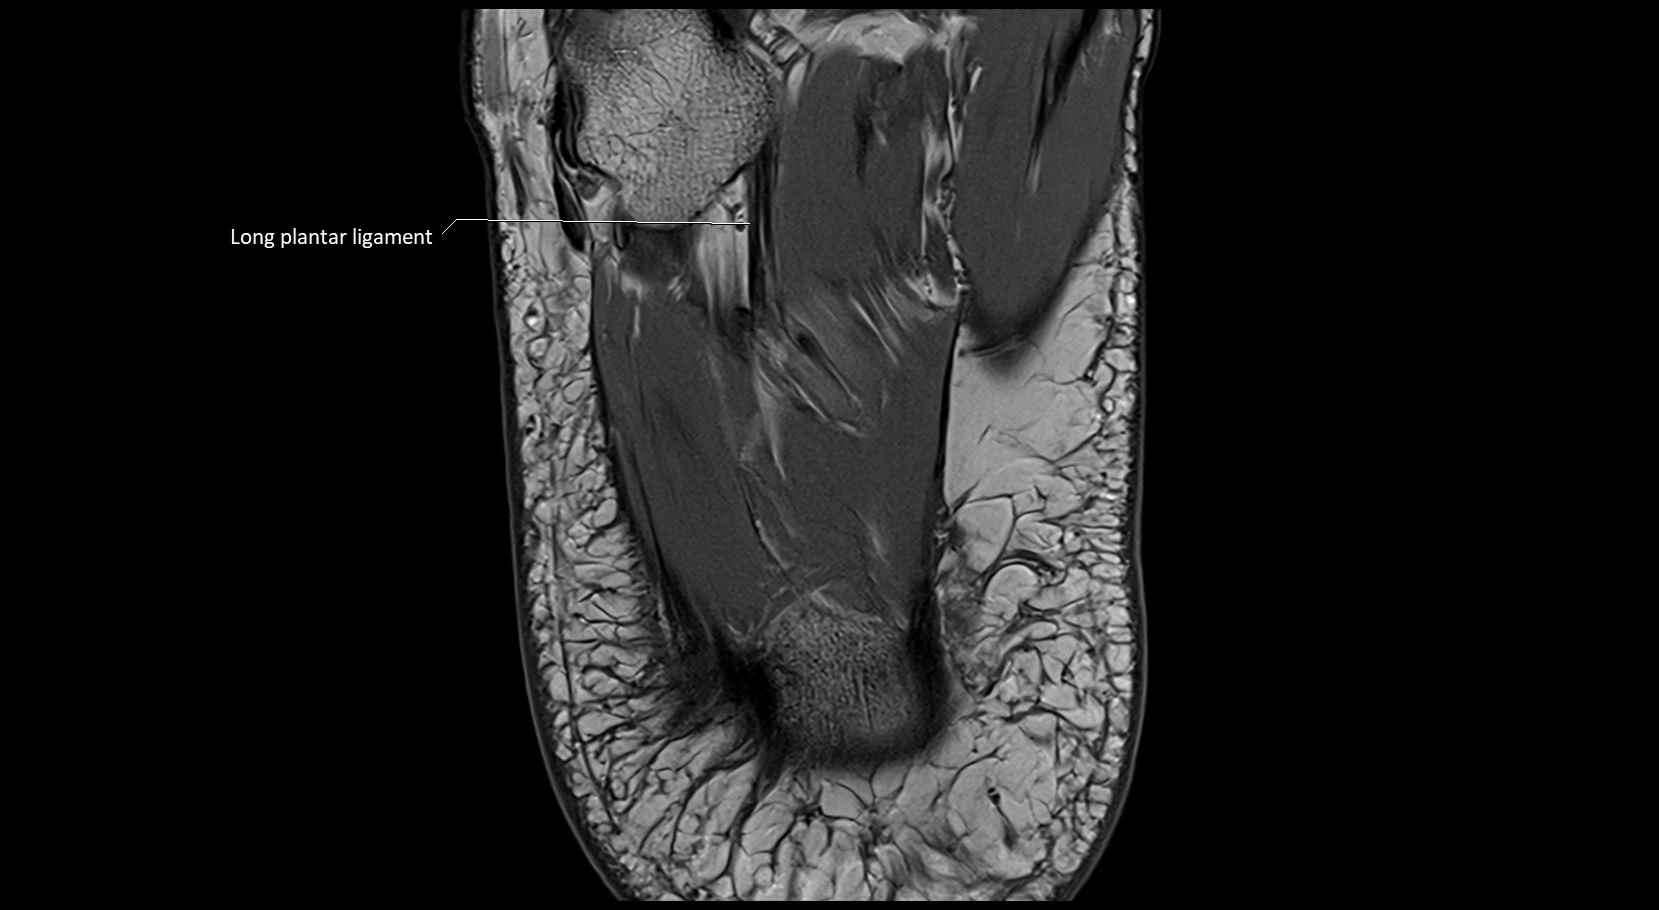

MRI image

image